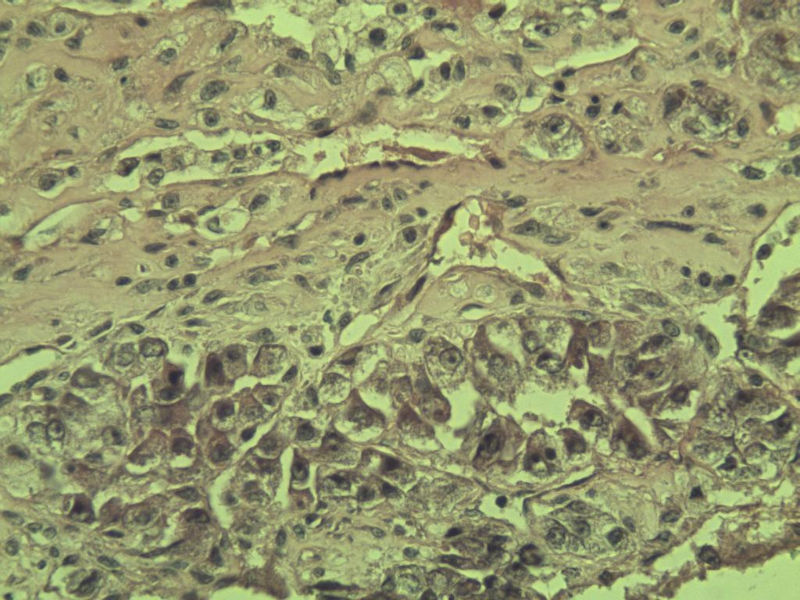

女 70岁 右颈部 头皮 多发皮下结节      取颈部部分结节送检 灰白小组织 1 块,直径 0.4 cm。 请问这个是什么?

肿瘤细胞大,上皮样,核空泡状,核仁明显,胞质嗜酸性或透明。

考虑:恶性黑色素瘤?

近心型上皮样肉瘤?

软组织透明细胞肉瘤?

上皮样多形性脂肪肉瘤?

等免疫组化标记!

此片染色欠佳,取材或切面也有问题,加大了诊断的难度,恶黑确实需要考虑,但其他一些转移癌也需要排除,比如肺癌之类的,还是期待免疫组化!